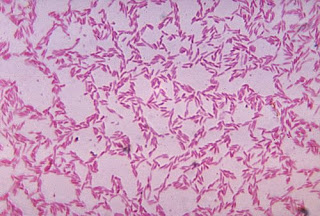

Bacteroides is a genus of Gram-negative, obligately anaerobic bacteria. Bacteroides species are non-endospore-forming bacilli, and may be either motile or non-motile, depending on the species. The DNA base composition is 40-48% GC. Unusual in bacterial organisms, Bacteroides membranes contain sphingolipids. They also contain meso-diaminopimelic acid in their peptidoglycan layer.